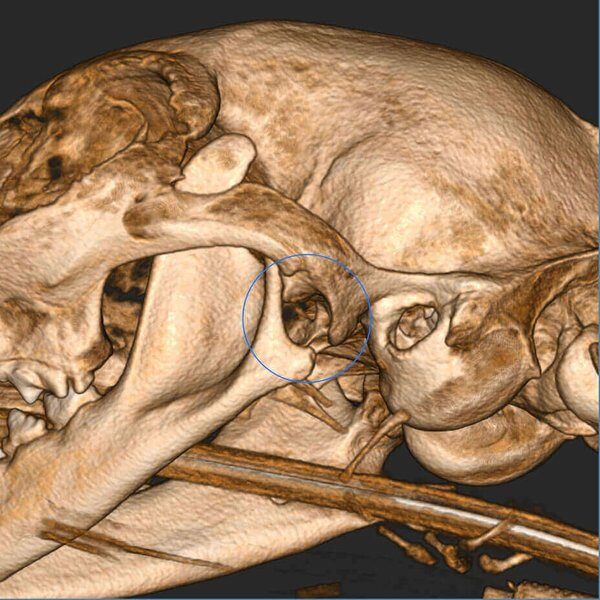

5G XL VET_Immagini Diagnostiche_Lussazione ATM_1

5G XL VET_Immagini Diagnostiche_Lussazione ATM_2

5G XL VET_Immagini Diagnostiche_Lussazione ATM_3

5G XL VET_Immagini Diagnostiche_Lussazione ATM_4

5G XL VET_Immagini Diagnostiche_Lussazione ATM_5

5G XL VET_Immagini Diagnostiche_Lussazione ATM_6